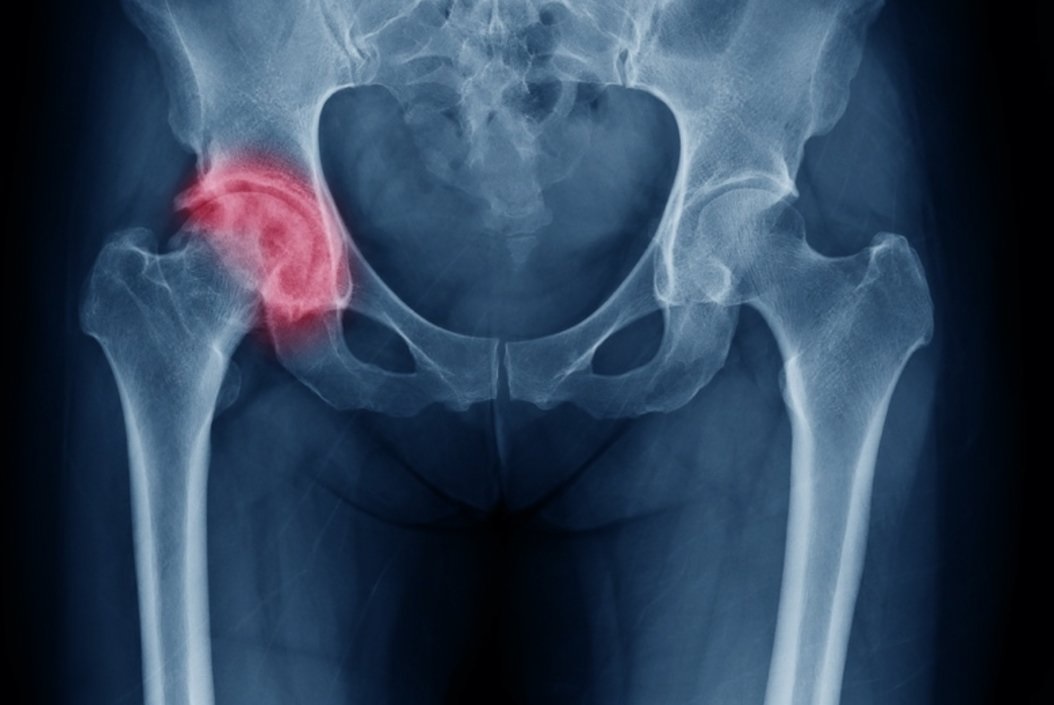

Η οστεοαρθρίτιδα του ισχίου είναι μια πολύ συχνή πάθηση που χαρακτηρίζεται από πόνο στο ισχίο και στη βουβωνική χώρα και δυσκαμψία. Αποτελεί μια  προοδευτική εκφυλιστική πάθηση που αφορά κυρίως ασθενείς μεγαλύτερης ηλικίας. Με την πάροδο του χρόνου ο χόνδρος μέσα στην άρθρωση του ισχίου γίνεται λεπτότερος και πιο εύθραυστος,   με αποτέλεσμα οι οστικές επιφάνειες της άρθρωσης  να έρχονται σε επαφή μεταξύ τους και να τρίβονται, προκαλώντας έτσι φλεγμονή με πόνο  και δυσκαμψία. Ένα από τα κύρια συμπτώματα της οστεοαρθρίτιδας του ισχίου είναι ο έντονος πρωινός πόνος και η δυσκαμψία, που μειώνονται αργά με ήπια δραστηριότητα και κίνηση. Ο πόνος μπορεί να ακτινοβολεί στο γλουτό, στην εξωτερική επιφάνεια του μηρού και προς τα κάτω στο πόδι έως το γόνατο. Ο πόνος επιδεινώνεται με την φόρτιση, την ορθοστασία και την ανύψωση από καθιστή σε όρθια θέση.